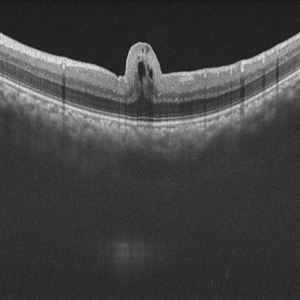

Giant RPE-rip

Sep 5 2021 by Hemanth Murthy, MBBS, MD, FASRS

Fundus fluorescein angiography of a 50 year-old patient with spontaneous giant RPE rip.

Photographer: Mr Veda Vyas

Imaging device: Heidelberg HRA

Condition/keywords: RPE-Rip